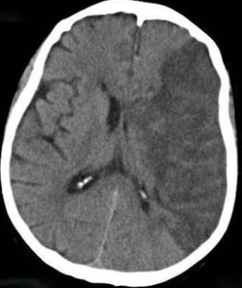

In the hyperacute setting of a stroke what may a brain CT scan show?

May be essentially normal :( but may show hyperdense middle cerebral artery for example